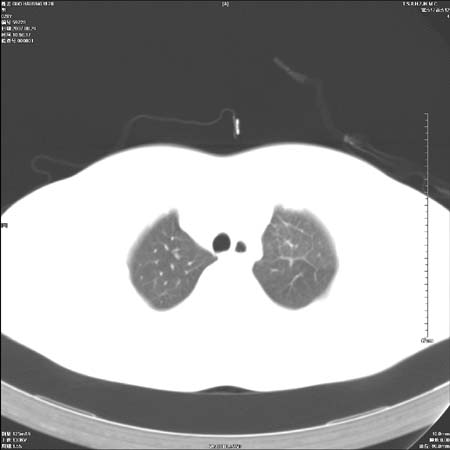

男性,28岁,体检发现左肺病变,患者只有背部隐痛感,哀哉,真不忍心下诊断啊。

左肺门区软组织肿块,左肺上叶支气管开口消失,纵隔内见肿大淋巴结,考虑左中心型肺部,可以做纤支镜取病理确认.

左肺肺门区肿块影,分叶明显:诊断肺癌应该没有疑问。

左肺肺门区肿块影,分叶明显,左肺上叶支气管开口受压,纵隔内见肿大淋巴结,考虑左中心型肺癌。

支持左上叶中央型肺癌伴纵隔淋巴结转移.

左上叶中央型肺癌伴纵隔淋巴结转移

左侧肺门区见一块状病灶可见分叶,纵隔内及左肺门见肿大淋巴结,应该是周围型肺癌而不是中心型肺癌,原因有以下2点,1未见阻塞肺气肿和阻塞性炎症,这么大肿块如果是中心型肺癌就是未分化型或小细胞型肺癌不出现阻塞性肺不张也应该有阻塞炎症或阻塞性肺气肿,2如果是中心型肺癌临床出现最早的症状是咳嗽(此时可无任何异常影象),而此人这么大肿块只有背部隐痛是体检才发现无法解释.

肿块形态影像支持左上叶中央型肺癌伴纵隔淋巴结转移。

左肺中心型肺癌并纵隔淋巴结转移!考虑为小细胞肺癌,没有手术机会了,只能进行放化了,疗效不错,但极易复发。没办法,现在肿瘤年轻化越来越明显了。